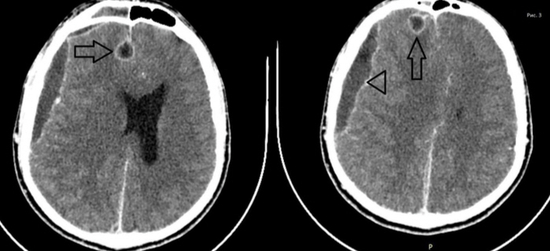

두개골 내 합병증의 유형 두개골 내 합병증의 주요 병소는 전두동염입니다.합병증 유형은 뇌수막염이 가장 많지만 여러 유형이 함께 나타나기도 하며 전두동이 성장하는 시기인 사춘기나 청년기 남성에서 많이 발생합니다.

경막 외 농양의 MRI 영상 경막 외 농양의 증상은 모호하고 전두동염과 비슷하기 때문에 전두부의 통증과 발열이 지속될 경우 의심해봐야 합니다.농양이 커지면 뇌압이 상승하여 국소운동장애, 감각장애, 발작을 보일 수 있습니다.CT, MRI로 진단하여 요추천자 중 정상적인 경우가 많습니다.

경막하농양(세모)과 뇌농양(시도장) MRI 영상경막하농양의 위치는 전두엽 부위에 많지만 대뇌 표면을 따라 전파되거나 산발적인 농양을 형성할 수 있습니다.초기에는 수막염 증상을 보이다가 급속히 악화되어 의식저하, 편마비, 발작을 보입니다.뇌농양의 경우 크기가 커져 뇌압상승과 함께 대뇌탈출, 농양파열로 사망에 이를 수 있습니다.